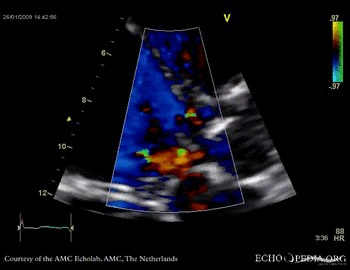

Aortic valve endocarditis with vegetation

Case description: This patient had endocarditis with an aortic valve vegetation

E00114.gif E00115.gif

PLAX showing an aortic valve vegetation PLAX Excentric aortic valve regurgitation